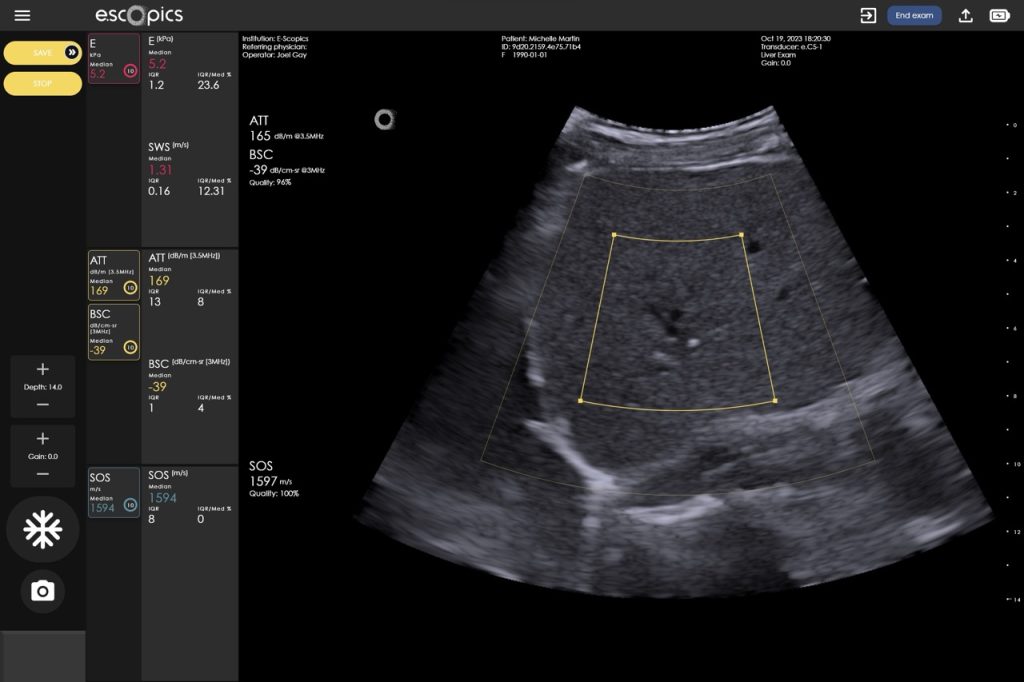

Reproducible and repeatable quantitative measurements performed in real time, under image guidance

The large regions of interest ensure increased accuracy of results, critical for system-level quality control.

2DTE – Sample Volume = 65 mL

Hepatoscope 2DTE (two-dimensional transient elastography)is the most advanced ultrasound technology for liver stiffness measurements (LSM), integrating both transient elastography (Catheline, Wu, and Fink 1999) and ultrafast ultrasound (Tanter and Fink 2014) implemented in an ultraportable format.

The Q.US Technology

Quantifying steatosis in the liver is the first step in the diagnosis of MASLD and primarily uses non-invasive ultrasound. Initially visual (qualitative), the assessment of fat in the liver has benefited from the development of quantitative ultrasound (QUS) which now offers objective measurements of steatosis-related parameters, surpassing subjective visual assessments.